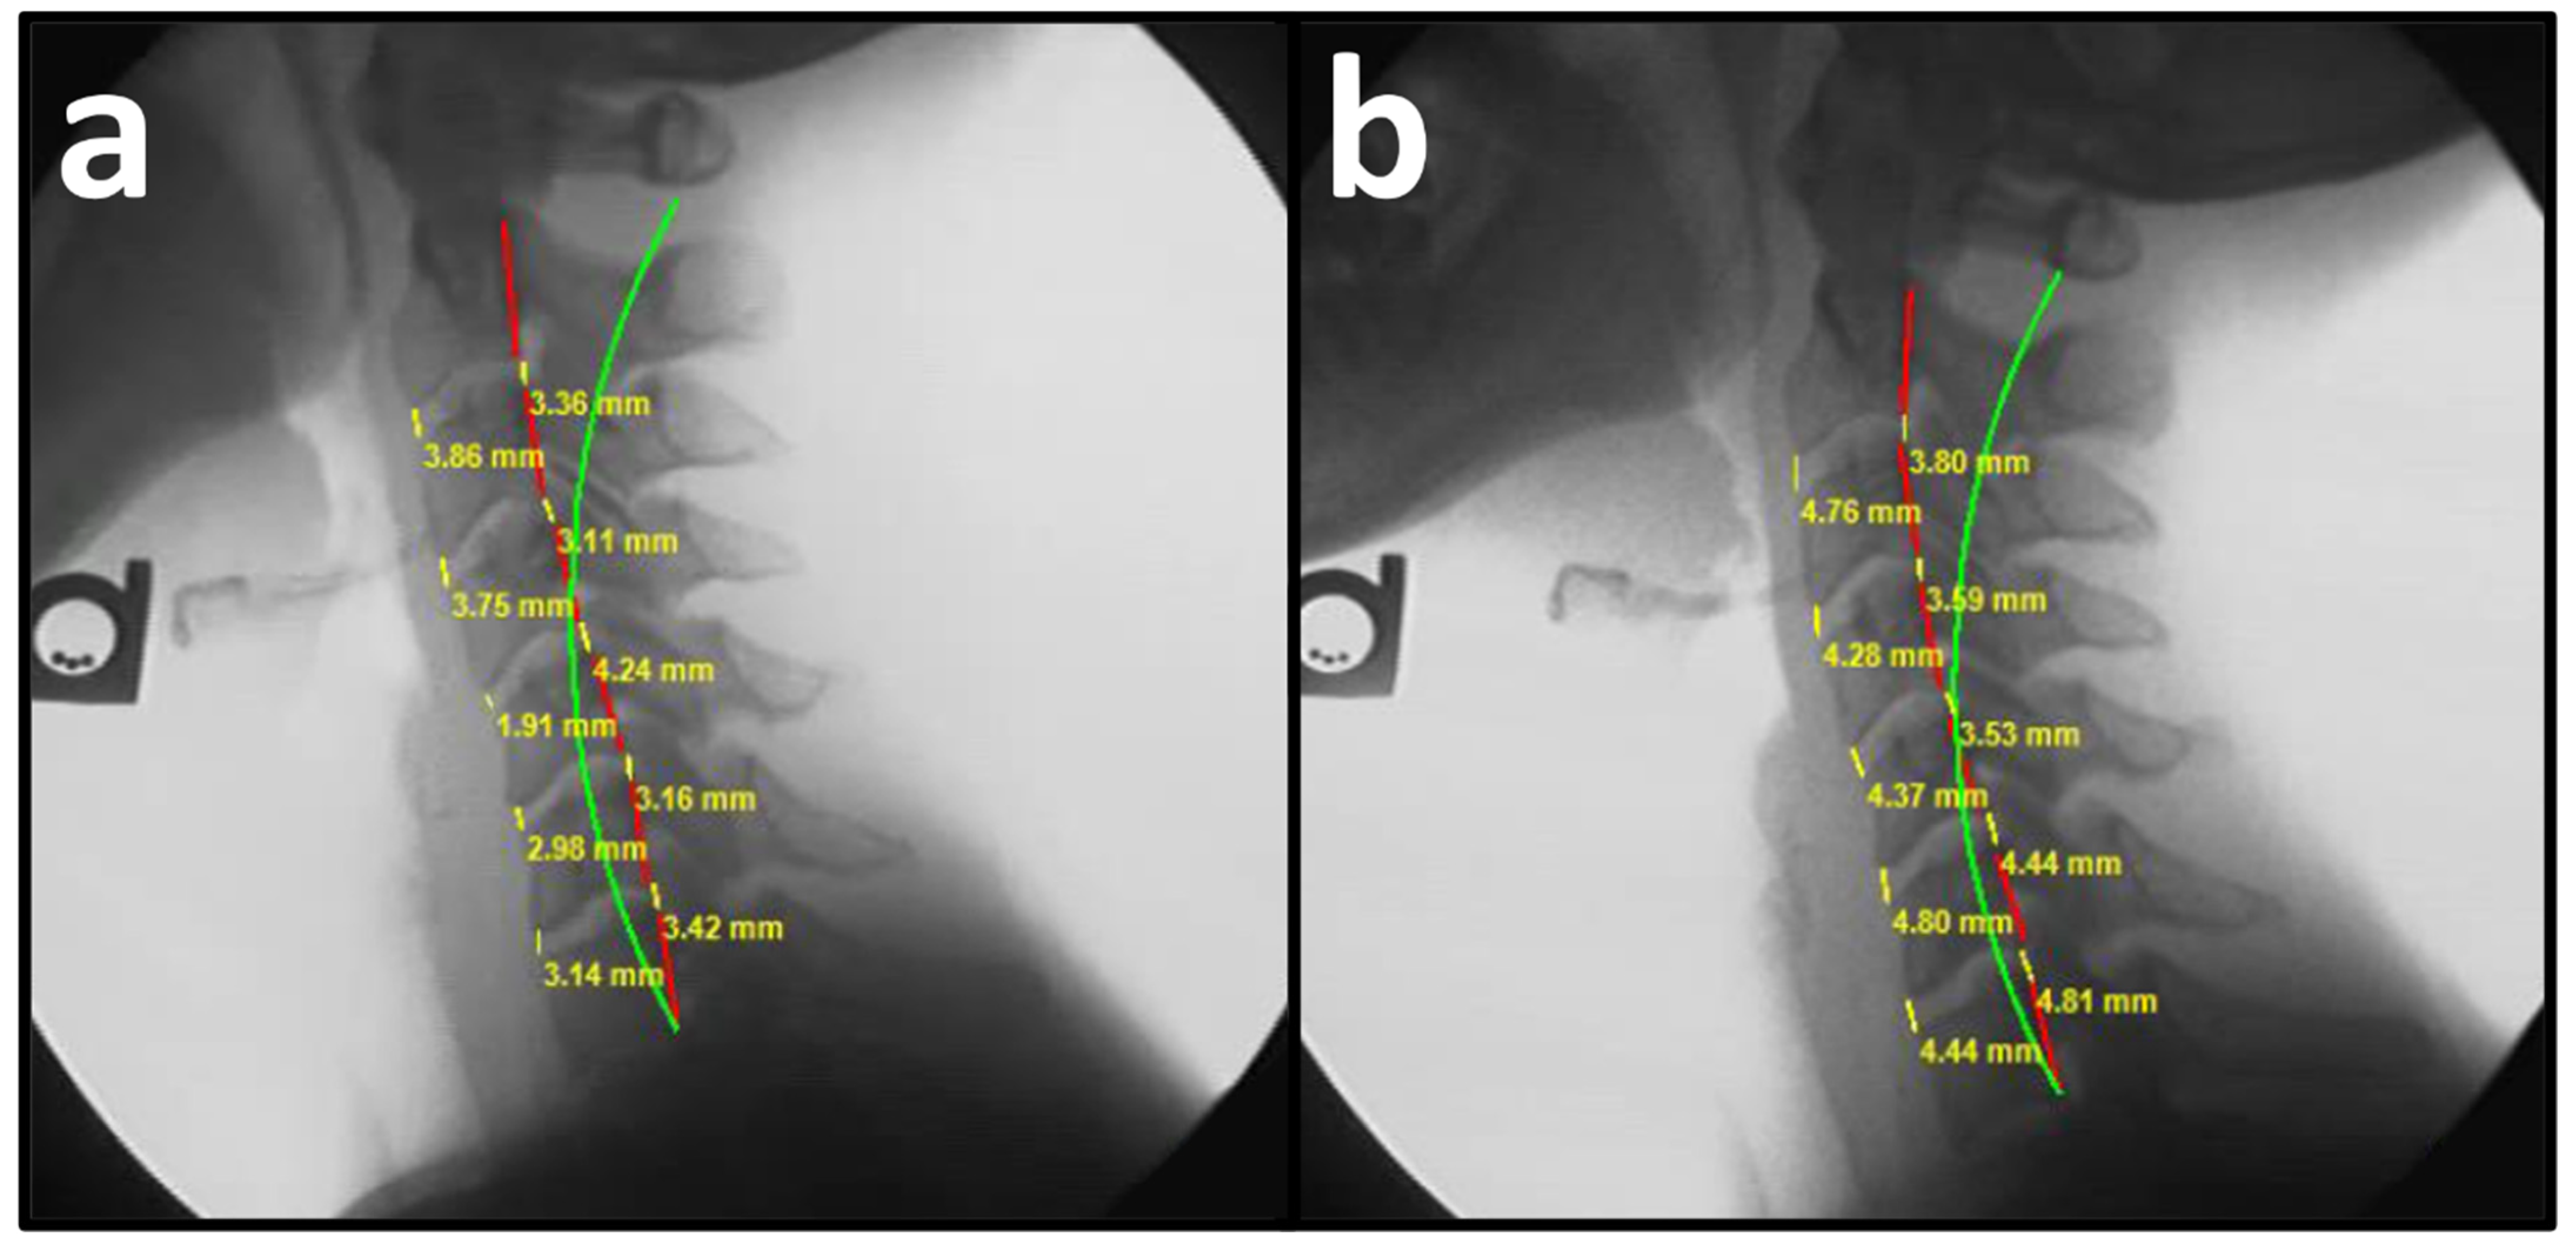

| Anterior Disc Height C2–C7 (mm) | 3.68 ± 0.20 | 5.19 ± 0.21 | 1.52 ± 0.59 | <0.0001 |

| ADH C2–C3 (mm) | 3.96 ± 0.21 | 5.40 ± 0.27 | 1.45 ± 0.96 | <0.0001 |

| ADH C3–C4 (mm) | 4.04 ± 0.25 | 5.39 ± 0.27 | 1.35 ± 0.98 | <0.0001 |

| ADH C4–C5 (mm) | 3.70 ± 0.31 | 5.23 ± 0.28 | 1.53 ± 0.91 | <0.0001 |

| ADH C5–C6 (mm) | 3.33 ± 0.28 | 4.87 ± 0.32 | 1.54 ± 0.88 | <0.0001 |

| ADH C6–C7 (mm) ** | 3.36 ± 0.29 | 5.08 ± 0.31 | 1.72 ± 0.93 | <0.0001 |

| Posterior Disc Height C2–C7 (mm) | 3.22 ± 0.15 | 4.35 ± 0.16 | 1.14 ± 0.50 | <0.0001 |

| PDH C2–C3 (mm) | 3.60 ± 0.23 | 4.81 ± 0.26 | 1.21 ± 0.99 | <0.0001 |

| PDH C3–C4 (mm) | 3.49 ± 0.20 | 4.49 ± 0.24 | 1.01 ± 0.87 | <0.0001 |

| PDH C4–C5 (mm) | 3.28 ± 0.23 | 4.31 ± 0.21 | 1.03 ± 0.93 | <0.0001 |

| PDH C5–C6 (mm) | 2.86 ± 0.21 | 3.99 ± 0.20 | 1.13 ± 0.71 | <0.0001 |

| PDH C6–C7 (mm) ** | 2.83 ± 0.23 | 4.19 ± 0.23 | 1.36 ± 0.78 | <0.0001 |